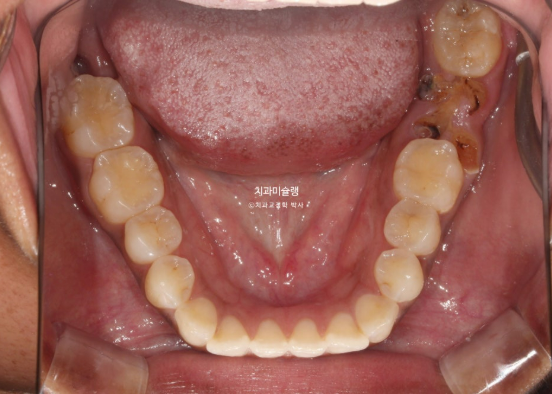

In the mandible, a molar was in a similar condition, with only the root remaining.

For the missing mandibular molar, ideally, the wisdom tooth could be moved forward to replace it. However, the wisdom tooth already showed root inflammation and was not in a healthy condition. Therefore, we decided to extract the wisdom tooth and proceed with orthodontic treatment, followed by implant placement in the molar region.

For the mandibular arch, we decided to extract the second premolar affected by dental caries.